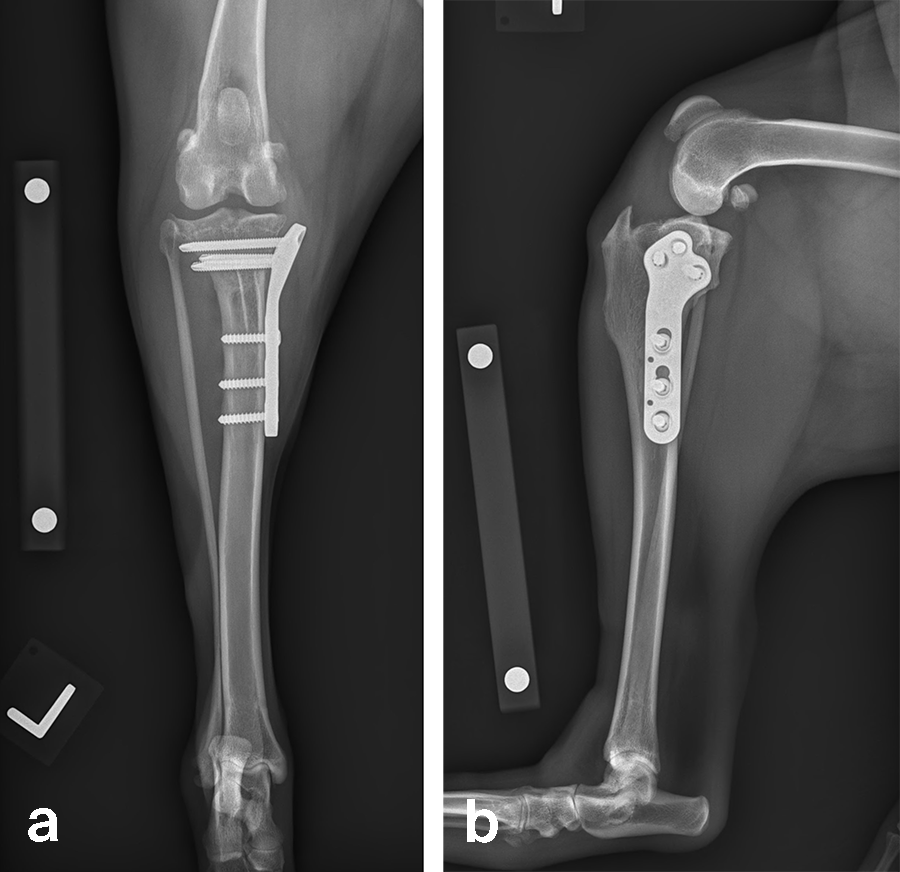

A 23.3 kg 3-year-old spayed female black Labrador Retriever presented with a history of chronic, progressive left pelvic limb lameness. Her clinical examination was suggestive of left cranial cruciate ligament (CCL) rupture. Medical and surgical treatment options were discussed with the clients. They elected to have Rosie’s knee treated with arthroscopy and TPLO.

Left stifle arthroscopy was performed and a partial CCL rupture with incompetent remand was identified. The remaining CCL was debrided with a motorized shaver. The meniscus was healthy/non-injured based on visual inspection and probing. Arthroscopy portals were closed, and exposure of the proximomedial tibia was performed.

Based on preoperative templating, a 21 mm radial saw blade was used to perform an osteotomy of the proximal tibia. The plateau was leveled to a final target slope of 5° and the osteotomy was stabilized with a 3.5 mm ARC TPLO plate.

In Rosie’s case, the plate fit was excellent and the TPLO was performed without complication. Postoperative radiographs illustrate excellent plate position and screw placement and compression across all aspects of the osteotomy. Rosie recovered uneventfully from surgery and at the time of recheck (7 weeks postoperation) was using the operated limb without visible lameness. The knee examination was unremarkable, and radiographs demonstrated robust healing of the TPLO.